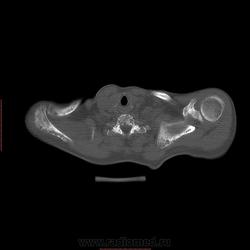

Пациент 1946 г.р., состоит на Д учете в онкодиспансере по поводу с-ч кожи (базалиома), прошел курс лучевой терапии, в 2009г на Ргенографии выявили образование 7 ребра, направили на Кт, на КТ (2009г) был выставлен д-з ГКО, пункционная биопсия не произведена. А сейчас вот такая картина, с множественными литическими очагами в костях грудного склета + образование 7 ребра, с отрицательной динамикой.

повторно взяли пациента, сняли кости таза, такая же картина- множественные очаги литической деструкции. Заключение: больше данных за миеломную болезнь.